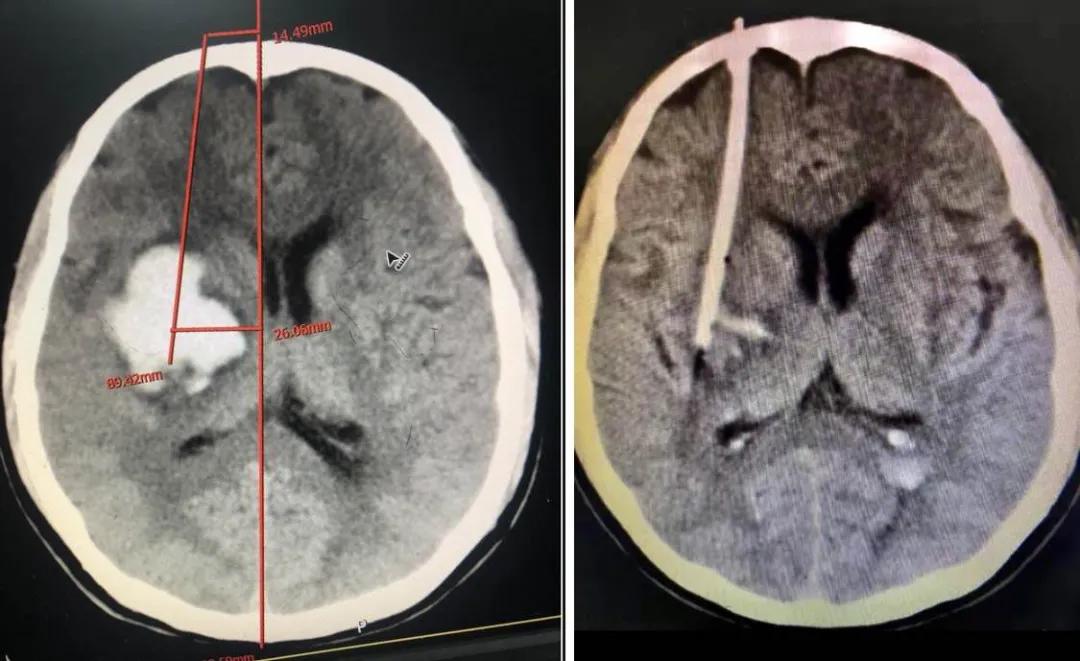

腔镜下颅内血肿清除术

患者林某,男性,82岁,反复头晕半个月,症状时好时坏,未引起重视,未进行治疗,4月27日突发右侧肢体无力,无不能言语,无人事不省,无口吐白沫、双眼上吊、四肢抽搐,无大、小便*禁失**。经查,该患者左侧额、颞、顶部亚急性硬膜下血肿,右侧顶部硬膜下少量出血未除。左侧额颞顶部硬膜下血肿清除术后,于2020.04.28在全身麻醉下行“内镜下颅内血肿清除术+脑积液漏修补术+颅骨修补术”。

术后降低颅内压及抗感染治疗,患者状态良好,病情得到恢复。

术前

术后